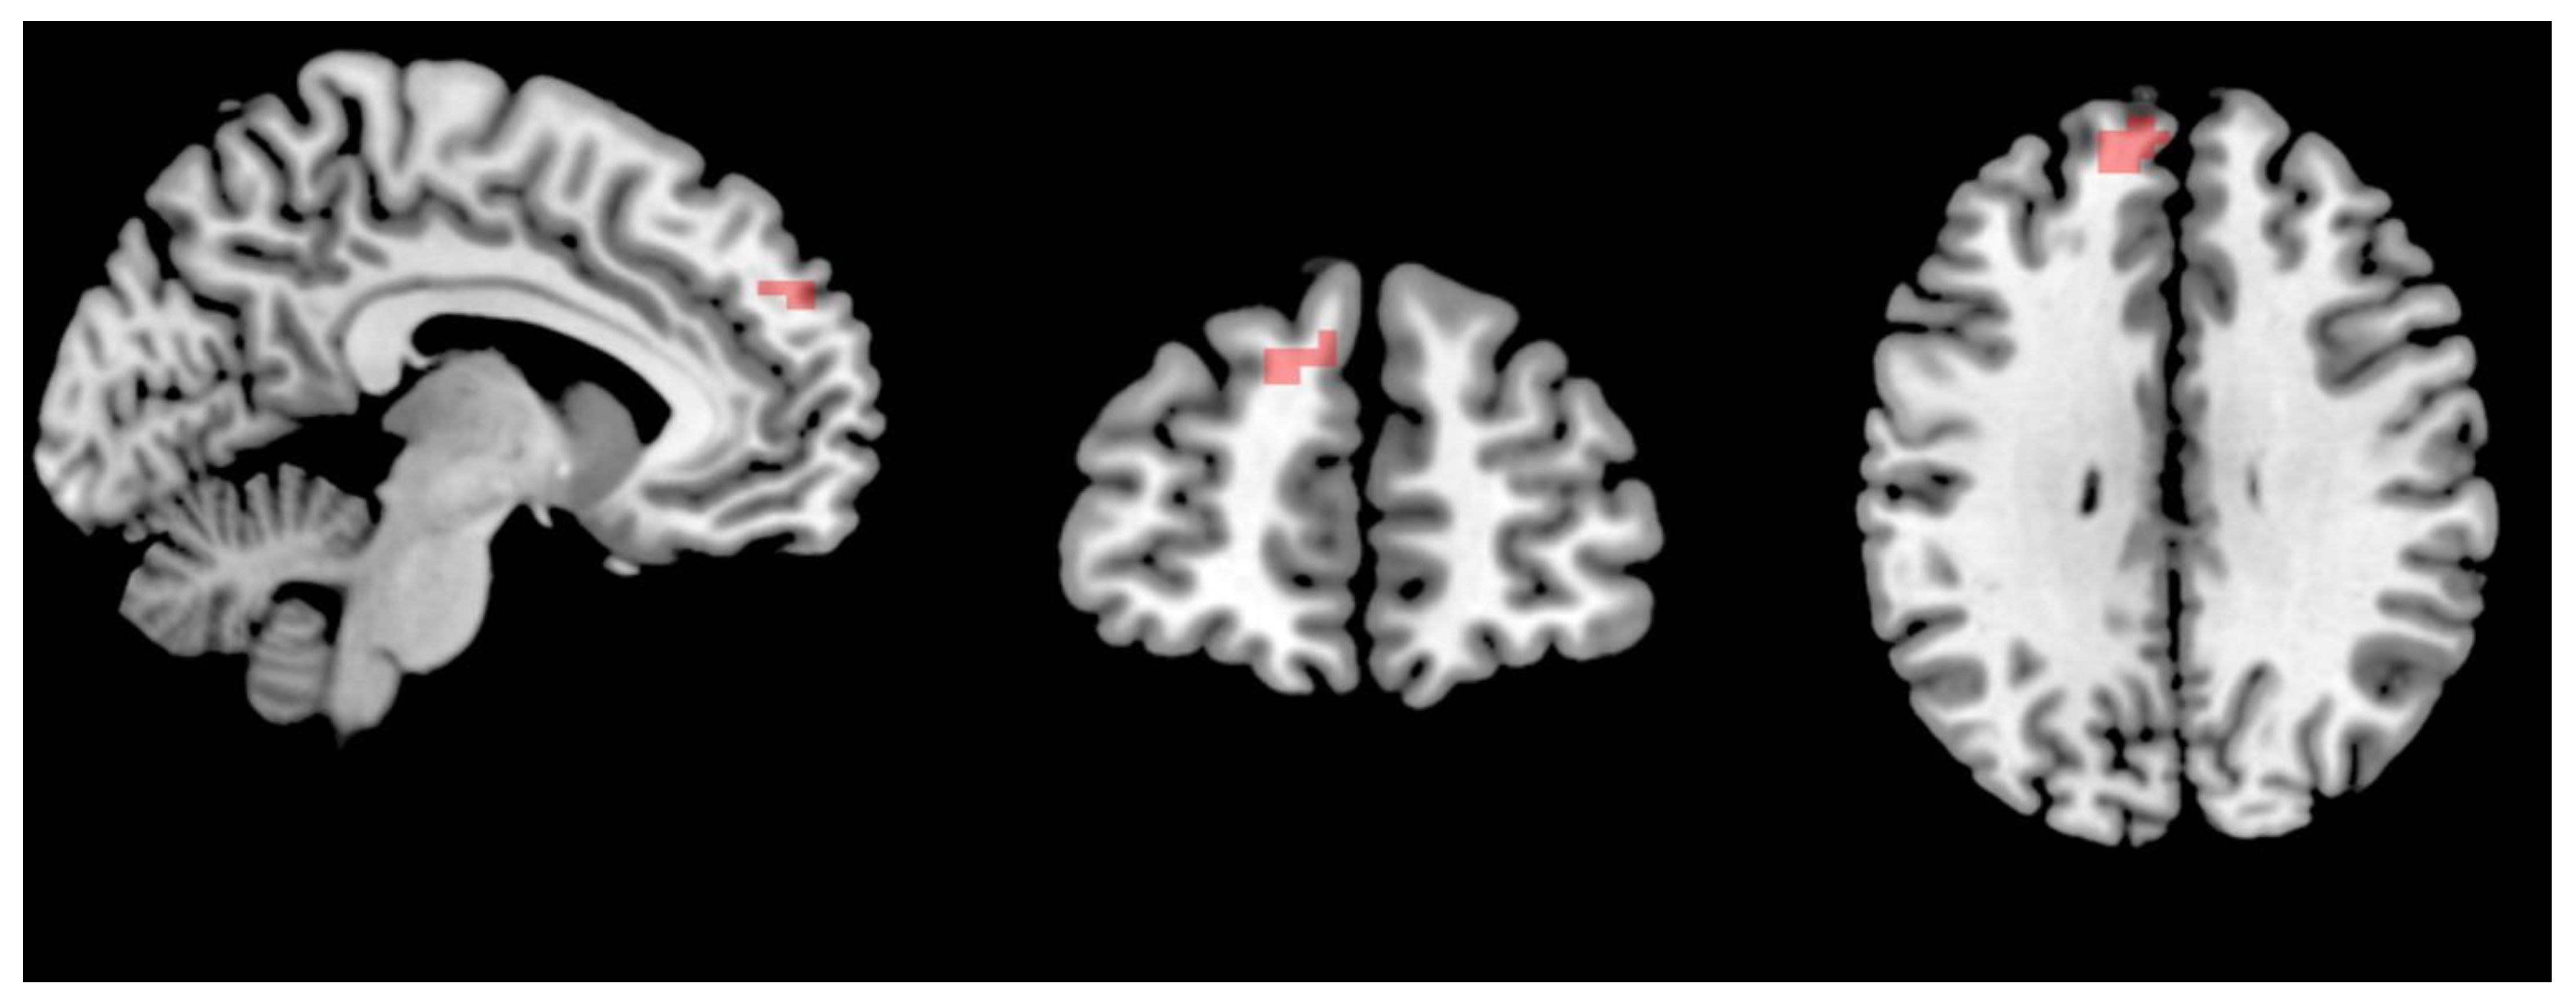

3.3. Changes in the Brain Networks and Correlation Analysis